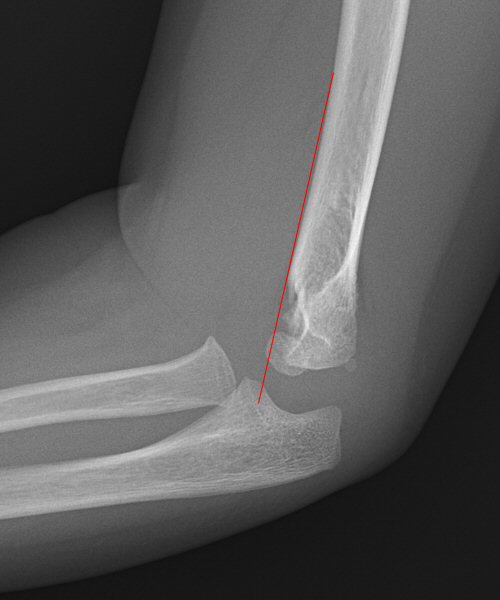

Suprakondylär humerusfraktur, Gartland 1.2, Rogers line delar capitulum radii, behandlades icke-kirurgiskt

• Rogers line/anterior humeral line måste åtminstone tangera capitulum radiis framkant, d.v.s.: [1]